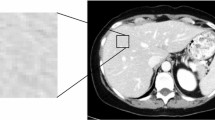

A total of 26 consecutive patients (12 F/14 M, mean age 58.5 ± 9.7 years) who met the criteria were recruited from our hospital between August 2014 and February 2016. All patients underwent baseline standard MRI followed by the first-line chemotherapy using FOLFOX (n = 9), FOLFIRI (n = 12), or XELOX (n = 5). The number of liver metastatic lesions was stratified into: 1–4 (10 patients), 5–10 (7 patients), or > 10 (9 patients). In all patients, 107 responding (Fig. 1) and 86 non-responding (Fig. 2) lesions were evaluated.